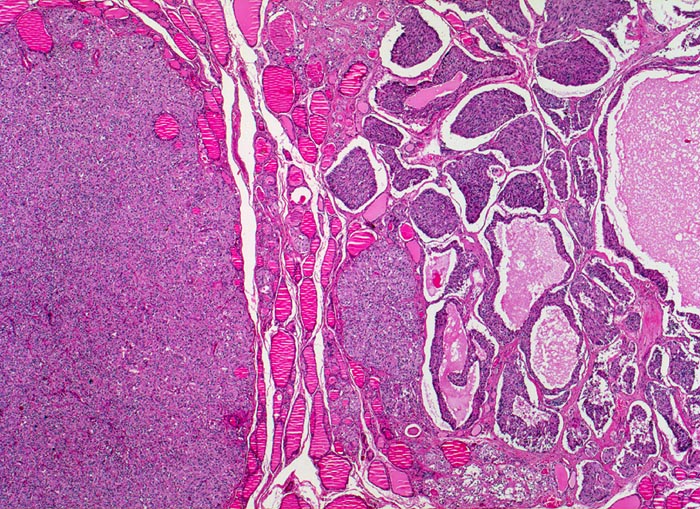

medulläres Schilddrüsenkarzinom

Solide, invasiv wachsende Tumorinfiltrate mit zystischen Hohlräumen. Stellenweise finden sich Inseln von Schilddrüsenparenchym innerhalb der Tumormasse.

Mehrere scharf begrenzte weisse Knoten in beiden Schilddrüsenlappen von bis zu 8mm Durchmesser.

Beim Vater der Patientin wurde ein bilaterales Phäochromozytom diagnostiziert und in der Folge eine multiple endokrine Neoplasie vom Typ 2A. Im Familienscreening wurde bei der Patientin eine Mutation im Ret-Protoonkogen nachgewiesen und eine prophylaktische Thyreoidektomie durchgeführt.